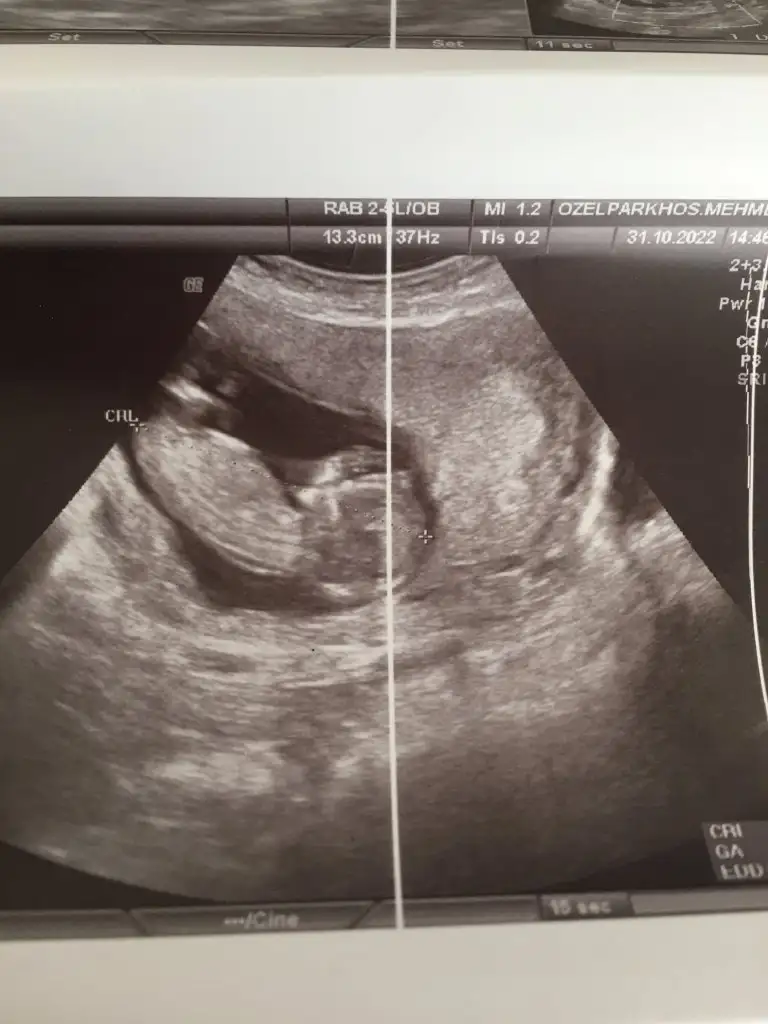

Merhaba 12 haftalık usg den nub yorumlayabilir misiniz?

• 92A2F75D-9DF9-45E3-B5E2-4990406FF123.webp

92A2F75D-9DF9-45E3-B5E2-4990406FF123.webp

29,1 KB · Görüntüleme: 101